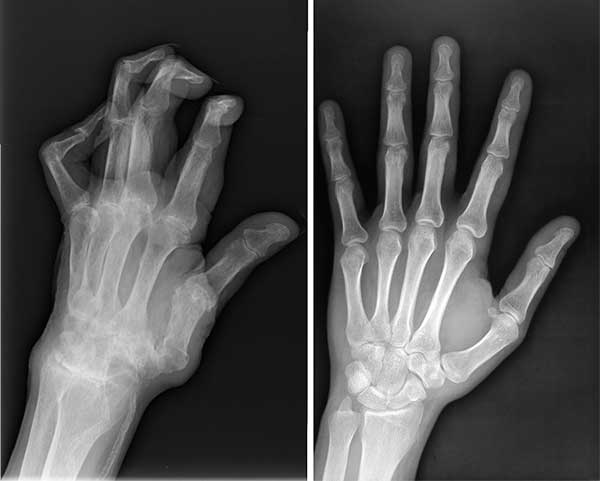

ไม่ใช่แค่หนูคนเดียวที่รอดเพราะผลิตภัณฑ์มหัศจรรย์ตัวนี้ สามีหนูป่วยเป็นโรคข้ออักเสบ ปลายนิ้วเสียหายมาก หนูเลยซื้อ Flexabon ให้เขาทาน พวกเราทานด้วยกันแล้วก็หายกันทั้งคู่เลยค่ะ

ภาพเอกซเรย์เปรียบเทียบก่อนและหลังทาน Flexabon ของสามี

ภาพเปรียบเทียบสภาพมือของสามีก่อนและหลังทาน Flexabon